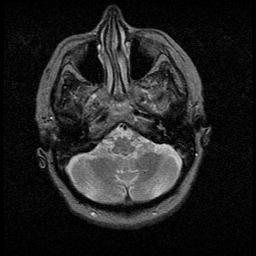

Huntington's Chorea, MR -- Slice #2